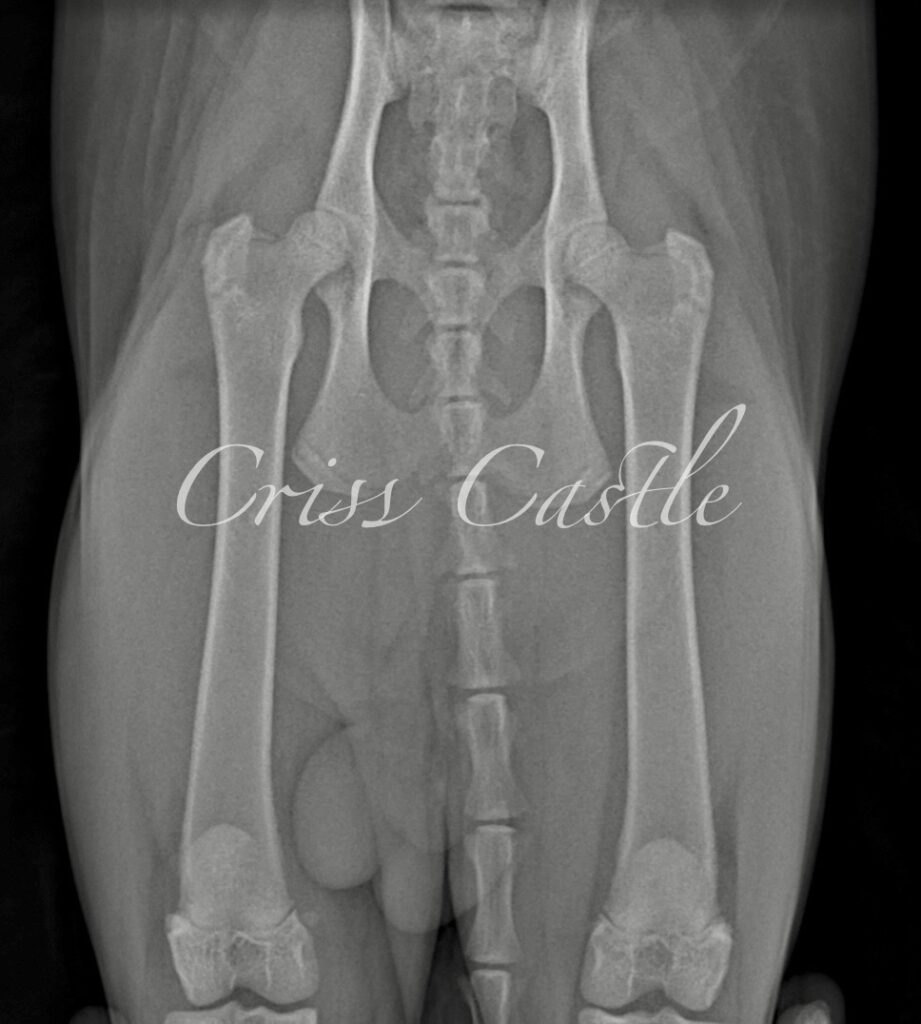

Hip X-Ray Results

Below are the current hip x-ray results for each Criss Castle breeding cat.

Note that as the cats continue to grow, this page may be updated with new results.